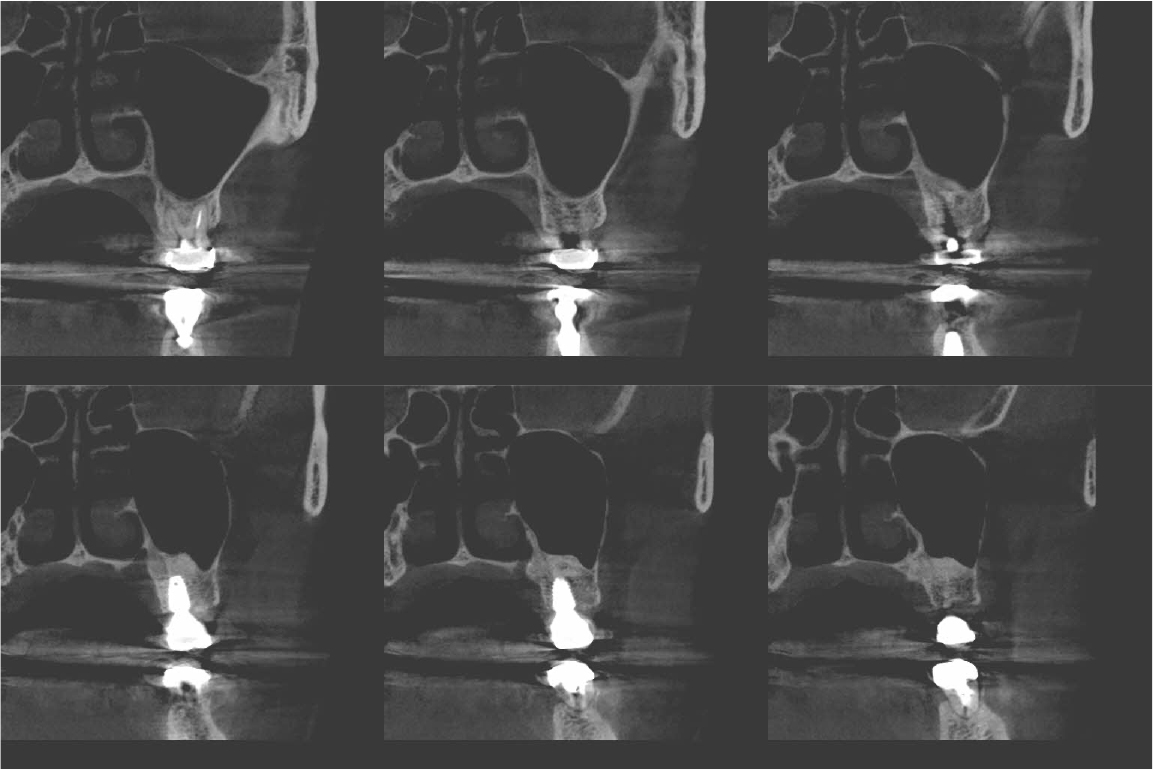

An implant with 5.0 mm diameter and 8.0 mm length (Superline; Dentium, Seoul, Korea) was placed with 0.5 cc of eproteinized bovine bone mineral (DBBM; Bio-Oss®, Geistlich, Wolhusen, Switzerland) by sinus elevation. The implant stability quotient (ISQ) after placement was 64 continually and the healing abutment was placed (6.5 mm diameter, height M size) (Fig. 4A, 4B). Postoperative antibiotics (Sultamox Tab. 500 mg; Alvogen, Seoul, Korea) and analgesics (Somalgen Tab. 370 mg; Alvogen), digestive agent (Beszyme Tab. 470 mg; Dong-A ST, Seoul, Korea) were prescribed for 5 days (30 min after meal). Gargle agent (G.U.M® Dental Rinse S; Sunstar, Osaka, Japan) with no toothbrushing was prescribed to drain and protect the operation area for 2 weeks. Postoperative cone-beam computed tomography (CBCT) showed a dome-shaped elevated membrane with a heterogeneous bone graft surrounding dental implants (Figs. 5 and 6). After 14 days, favorable healing gingiva was confirmed with the stitch-out process (Fig. 7).

Numerous studies have evaluated protocols to increase the success rate of immediate implant placement after extraction. The primary stability of immediate implant placement has been reported to be the most important factor.15 Lioubavina-Hack et al.16 presented at least 3−5 mm residual alveolar bone under the extraction socket as the requirement for successful placement. In this case, a 5 mm residual bone height would be sufficient for primary stability; however, this is not a satisfactory vertical bony height for implant placement. Therefore, the alveolar crestal approach and hydraulic sinus lift technique with DBBM were used for the elevation of the maxillary sinus membrane. As favorable primary stability was guaranteed, the healing abutment was placed consecutively. The sinus membrane was not elevated symmetrically, as ordinary in the case of hydraulic sinus lift, but the fixture was surrounded by sufficient bone graft material verified by CBCT (Fig. 6).

Previous studies have evaluated the positional relationship between the surrounding bone and the fixtures. Vignoletti et al.17 and Caneva et al.18 have reported that buccal bone resorption was significantly lower in the case of implants placed close to the lingual wall. Chen et al.19 also reported that a bone graft between the fixture and the buccal wall, in case of sufficient residual buccal bone thickness, could inhibit horizontal bone resorption; however, vertical bone resorption would be inevitable. In this case, more than 2 mm of residual buccal bone and fixtures placed close to the lingual wall are confirmed by CBCT (Fig. 6). These findings would guarantee favorable surrounding alveolar bone volume after 4 years of implant placement.